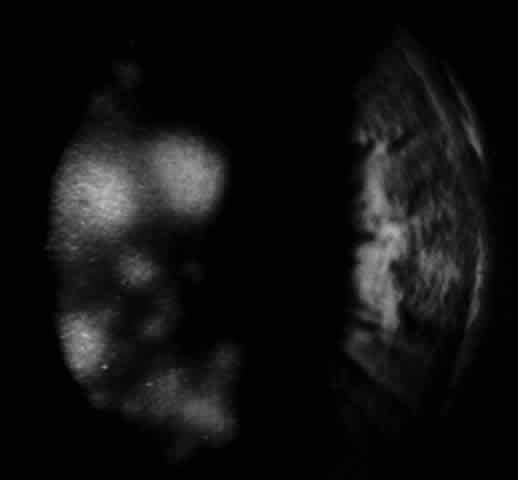

In 1986, Matoba and associates reported 7 patients with purported EBV stromal keratitis, but only 3 of the patients had clinical symptoms of IM or evidence of recent seroconversion.69 In one of the patients, heterophil antibody-positive IM preceded by 1 week the onset of chronic multifocal keratitis. When the authors first examined the patient in referral 9 months later, they found multiple, discrete, anterior stromal opacities in the patient's left eye. In another patient, bilateral, patchy, deep peripheral infiltrative keratitis and a fourfold decrease in antibody against EBV viral capsid antigen were documented at the time of referral 5 months after an “infectious mononucleosis-like illness” associated with bilateral red eyes and photophobia. In another patient, the authors state that IM preceded subepithelial infiltrative keratitis in the left eye by 1 month. When examined 8 months after onset of the keratitis, the patient's left cornea showed features of multifocal anterior stromal and deep peripheral stromal keratitis. Although the other 4 patients in this series did not show evidence of recent EBV seroconversion, their keratitis appeared similar to that of the patients with documented IM. On clinical grounds alone, Matoba and associates postulated that the development of EBV keratitis did not depend on recent EBV infection, but could occur in the chronic carrier state. To summarize the authors' findings in the combined group of 7 patients, the interstitial keratitis appeared in 4 patients as unilateral, multifocal, discrete, sharply demarcated, anterior stromal opacities, 0.1 to 2 mm in diameter, with either a blotchy pleomorphic (Fig. 2) or granular ringlike appearance (Fig. 3), in two patients as bilateral, multifocal, full-thickness or deep stromal peripheral infiltrates reminescent of luetic keratitis (Fig. 4), and in 1 patient with features of both. No patient tested had showed serologic evidence of acute systemic HSV or adenovirus infection. Both patients with keratitis restricted to the peripheral cornea had bilateral disease but lacked serologic evidence for syphilis (nonreactive MHA-TP). Five patients had mild or moderate corneal stromal vascularization. Two patients showed corneal epithelial granularity overlying the stromal opacities.

Fig. 4. Multifocal deep peripheral corneal stromal infiltrates in a 17-year-old man. (Matoba AY, Wilhelmus KR, Jones DB: Epstein-Barr viral stromal keratitis. Ophthalmology 93:746, 1986)